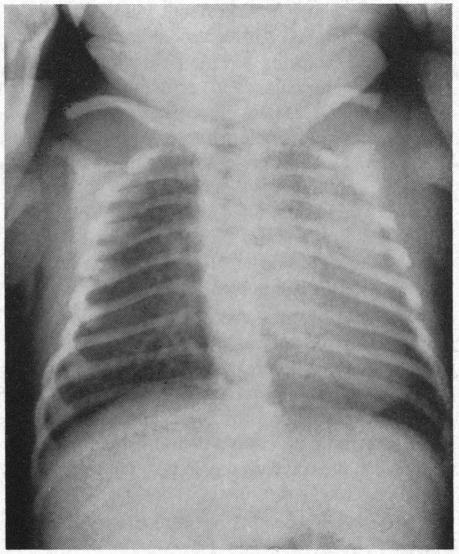

Syndrome of cyanosis, symmetry and splenic agenesis.

Calif Med. 1966 Feb;104(2):120-3.

Syndrome of cyanosis, symmetry and splenic agenesis.青紫、对称及脾缺如综合征。